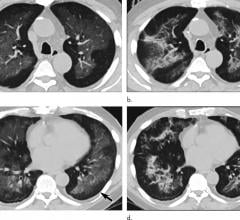

August 27, 2020 — Injuries to the lungs from vaping have suggestive patterns on computed tomography (CT) scans that ...